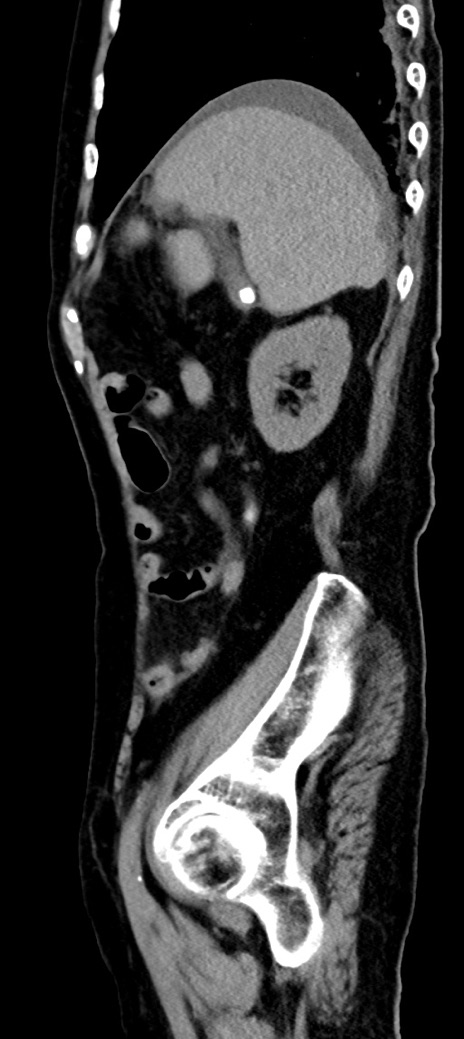

横断像

他院CT